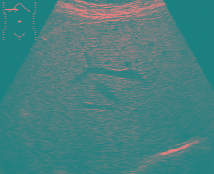

In primele stadii ale bolii nu exista simptome, cei mai multi pacienti sunt diagnosticati intamplator, cu ocazia unui examen ecografic abdominal de control, unor analize de sange de rutina ori in cadrul unui consult medical pentru alte acuze decat hepatice.

Steatoza hepatica se diagnosticheaza de catre medicul specialist sau medicul de familie dupa un consult clinic competent cu anamneza amanuntita, examen ecografic abdominal si profil biologic hematologic, biochimic si imunologic, alte investigatii, pentru excluderea altor hepatopatii mai grave: ciroza hepatica, cancer hepatic, metastaze hepatice, hepatite virale, hepatite toxi-nutritionale sau autoimune, afectiuni biliare sau pancreatice.

– Sa efectueze examen ecografic abdominal la 6 luni / 1 an sau la indicatia medicului.